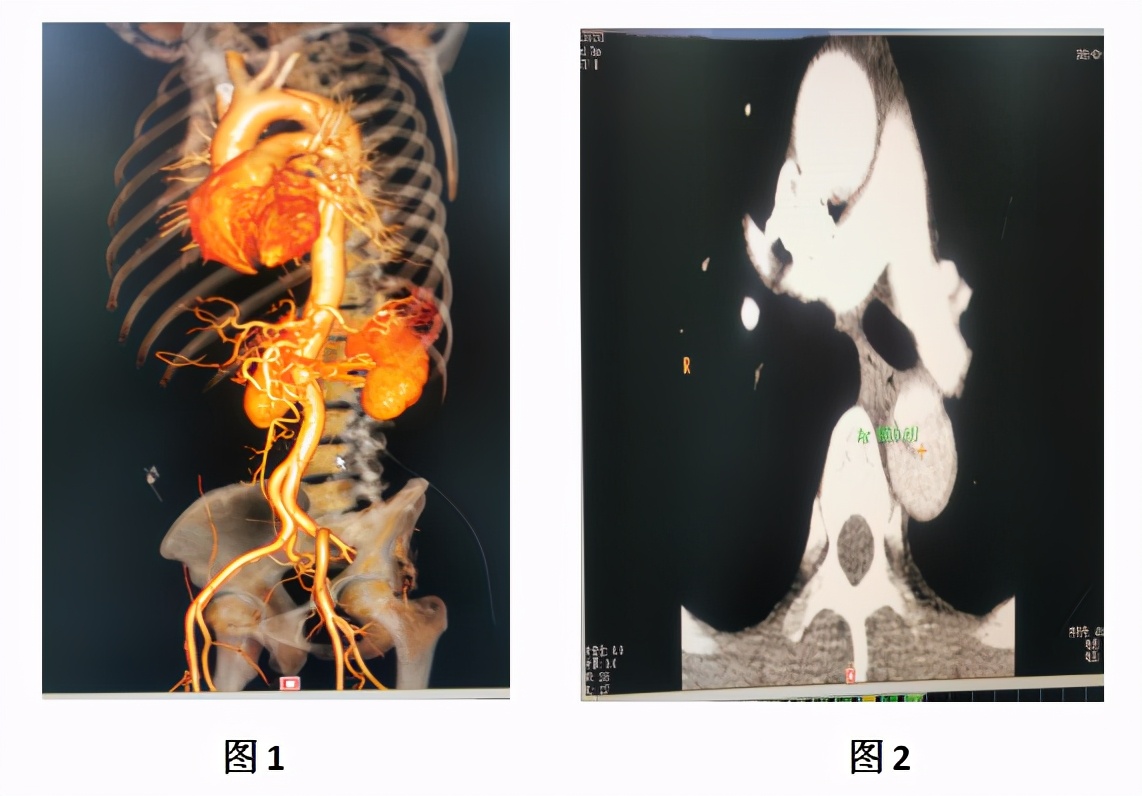

图1、图2为术前患者CTA检查

3月11日,患者血压、脉搏、心率等各项生命监测指标控制良好,病情趋于稳定。罗湖医院血管外科主任黄智勇主任带领团队为患者行胸主动脉造影+胸主动脉腔内隔绝术。术中见主动脉夹层(stanford B型),定位释放支架,精准定位、精确制导,效果立竿见影,无缝连接,假腔完全消失,无内漏,血流通畅(见图3)。